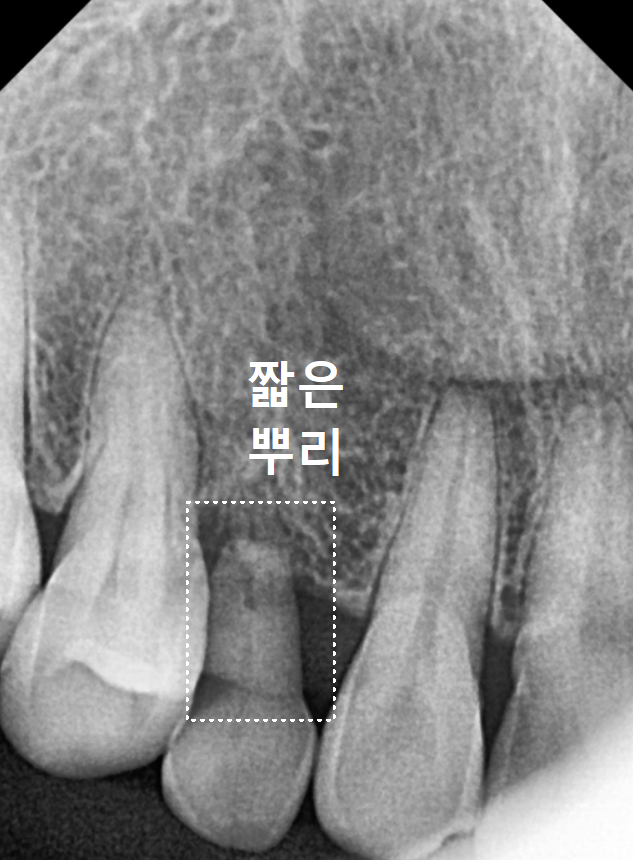

엑스레이를 찍어보니

아주 짧고 가느다란 유치 뿌리가 보입니다.

일반적인 송곳니들은

다른 치아들에 비해 뿌리가 긴 편인데,

유치는 영구치에 비해

상대적으로 뿌리가 짧다보니,

사용할 수 있는 기간이 더 짧을 수 밖에 없어요.

우선 가장 큰 차이는 뿌리의 길이에 있습니다.

유치는 영구치보다 뿌리가 훨씬 짧다 보니

성인의 강한 씹는 힘을 수십 년간

온전히 견뎌내기에는

아무래도 무리가 따를 수밖에 없답니다.